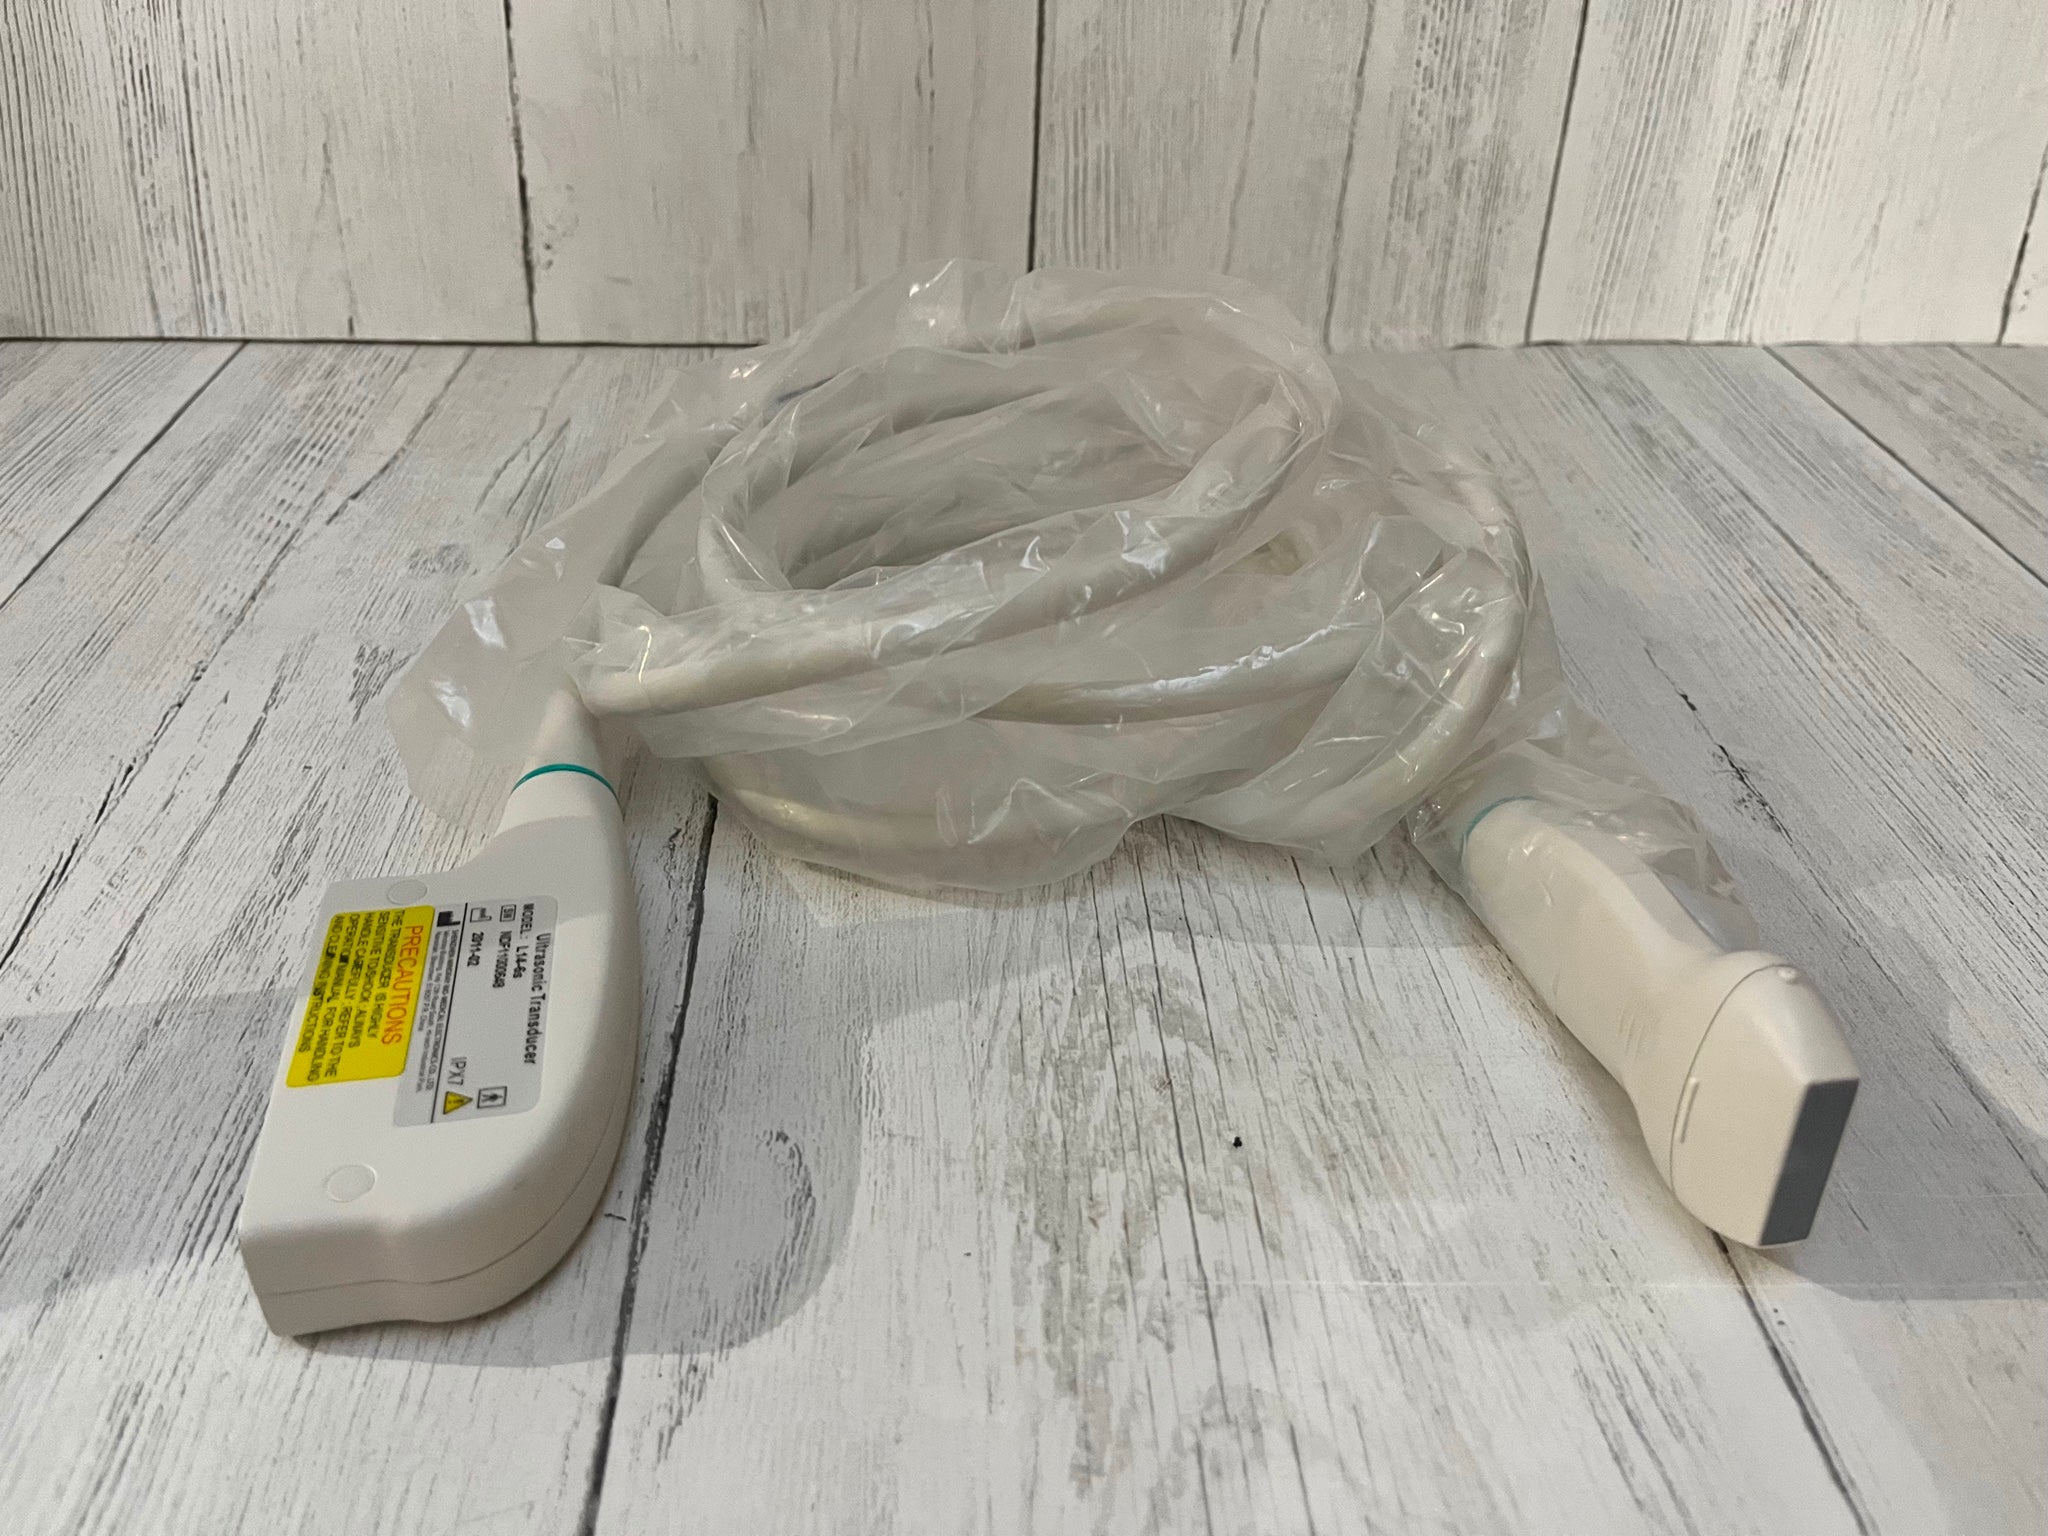

Probe 2: 7.5MHZ Transvaginal probe:gynecologic examination

The Ultrasound Scanner utilizes cutting-edge imaging technology, allowing for detailed and accurate evaluations during pregnancy. With capabilities for both convex and transvaginal scanning, this device provides versatile options for healthcare professionals. It is essential for monitoring fetal development and ensuring the health of both the mother and the unborn child. Doctors can easily select the appropriate probe, enabling them to capture high-resolution images that are critical for diagnosis and treatment.